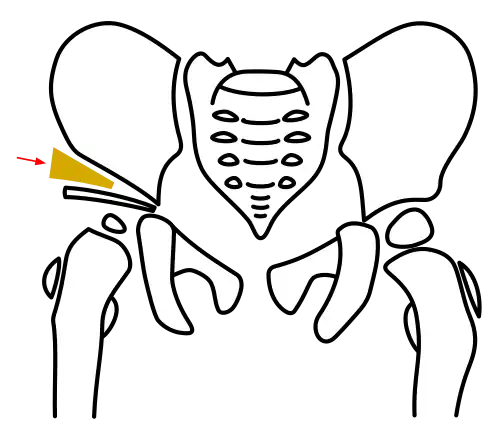

Acetabuloplasty, Step 2: Tilting the acetabular fragment downward

Acetabuloplasty, Step 2: Tilting the acetabular fragment downward -

In the Pemberton technique, under continuous X-ray guidance, the ilium is notched approximately 5 mm above the acetabular rim using a flat chisel, and the osteotomy is extended toward the Y-shaped physis. The acetabular fragment is then tilted downward and forward under X-ray control to achieve anatomical reconstruction.[7][10]

Dega osteotomy

The Dega osteotomy also extends toward the Y-suture but uses specialized curved chisels to achieve a spherical detachment of the fragment, matching the acetabulum's curvature. Originally, Dega tilted the fragment only laterally, but modern practice often includes an anterior tilt, similar to the Pemberton method.[9]